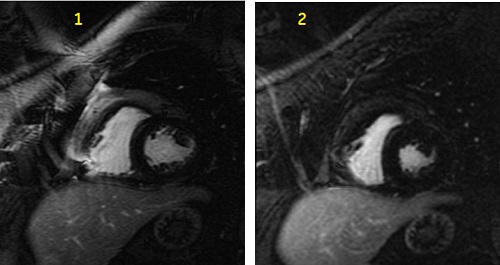

Figure 3. Comparison of heart images with and without SPECIAL

Table 1. Image legend

NumberDescription

1Standard MDE images.

2MDE images with SPECIAL fat suppression that demonstrates peri-cardial enhancement.